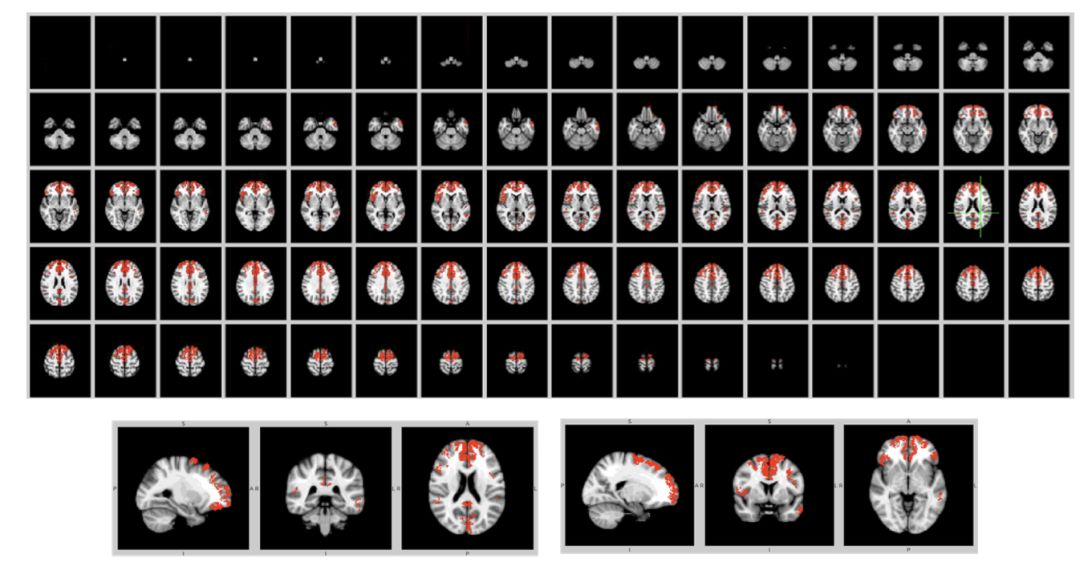

这里给出了 148 大脑区域中的 24个大脑区域 embedding的可视化结果,患者是红色,正常人是绿色,加上 graph infomax 的损失之后,正常人和患者的有些大脑区域更加线性可分。

在大脑的 148个区域中,我们发现了 31个比较线性可分的大脑区间,在上图中的标记为红色。